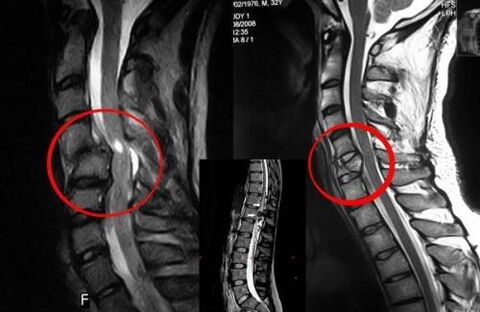

- CT eta MRI;

- erresonantzia magnetiko nuklearra.